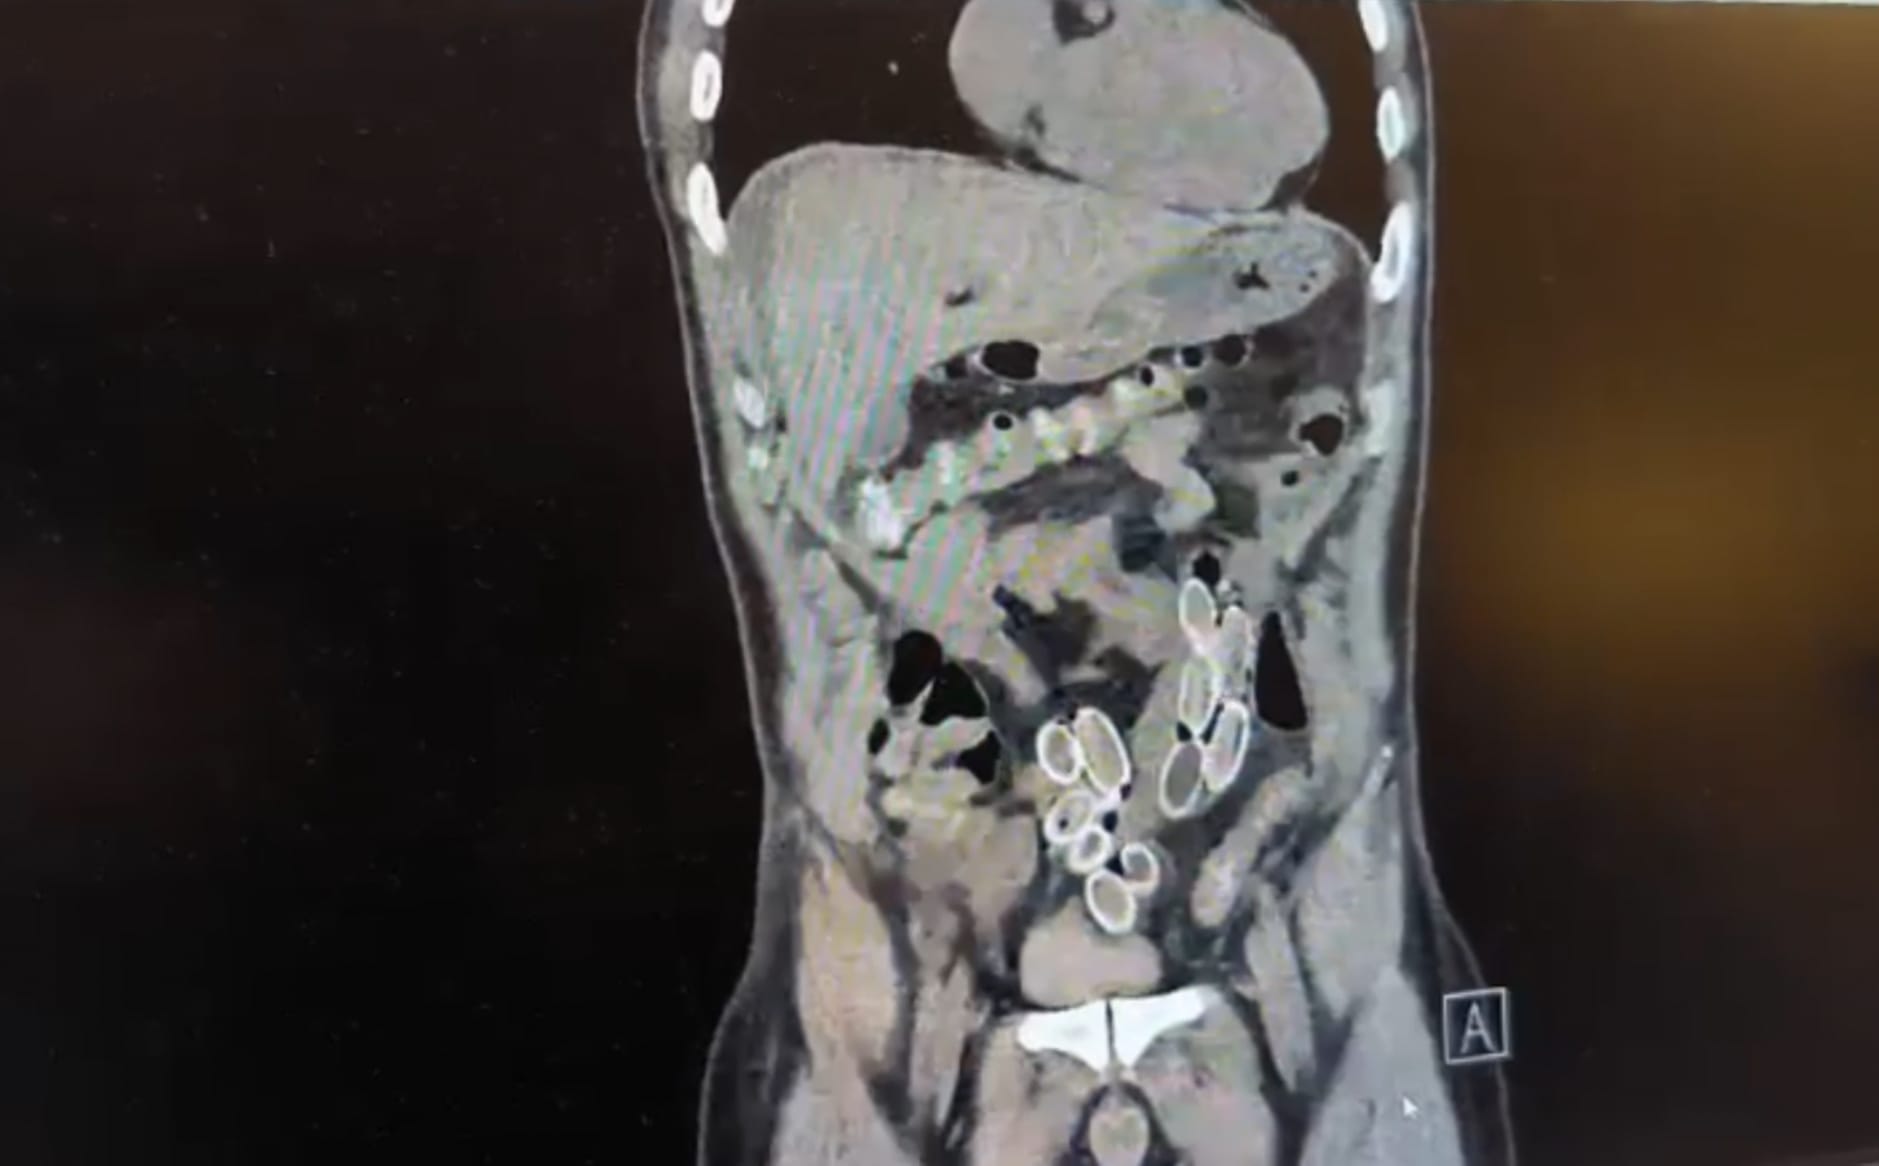

İstanbul’un Beşiktaş ilçesinde akıllara durgunluk veren bir olay meydana geldi. Fas’tan, yaklaşık 3 bin kilometre uzaklıktan uçakla Türkiye’ye gelen Cüneyt G, 2 gün sonra karın ağrısı şikayetiyle hastaneye gitti. Yapılan müdahalenin ardından Cüneyt G.’nin tomografisi çekilirken şüphelinin mide ve bağırsaklarında yabancı madde tespit edilmesi üzerine hastane yetkilileri durumu polis ekiplerine haber verdi.

İhbar üzerine olaya ilişkin çalışma başlatan polis ekipleri, doktorlarla görüşme gerçekleştirdi. Ameliyata alınan şahsın mide ve bağırsaklarından, toplam ağırlığı 259,7 gram olduğu öğrenilen 49 esrar macunu çıkarıldı. Şüpheliye ait 1 adet cep telefonu da hastane yetkilileri tarafından polis ekiplerine teslim edildi.